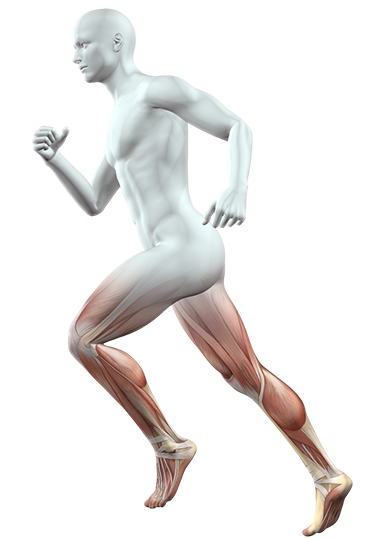

At Ashwini Hospital, our team of expert therapists is dedicated to helping patients recover, heal, and regain their quality of life.

A fracture can be treated in several ways depending on the severity of the injury and the location of the fracture. The most common methods of treatment include:

We understand that injuries and acute pain can happen unexpectedly. Our emergency physiotherapy services are designed to provide prompt and effective care to help you manage.

neck pain

shoulder pain

hip pain

knee pain

elbow pain

tricep pain

hand pain

foot pain

ankle pain